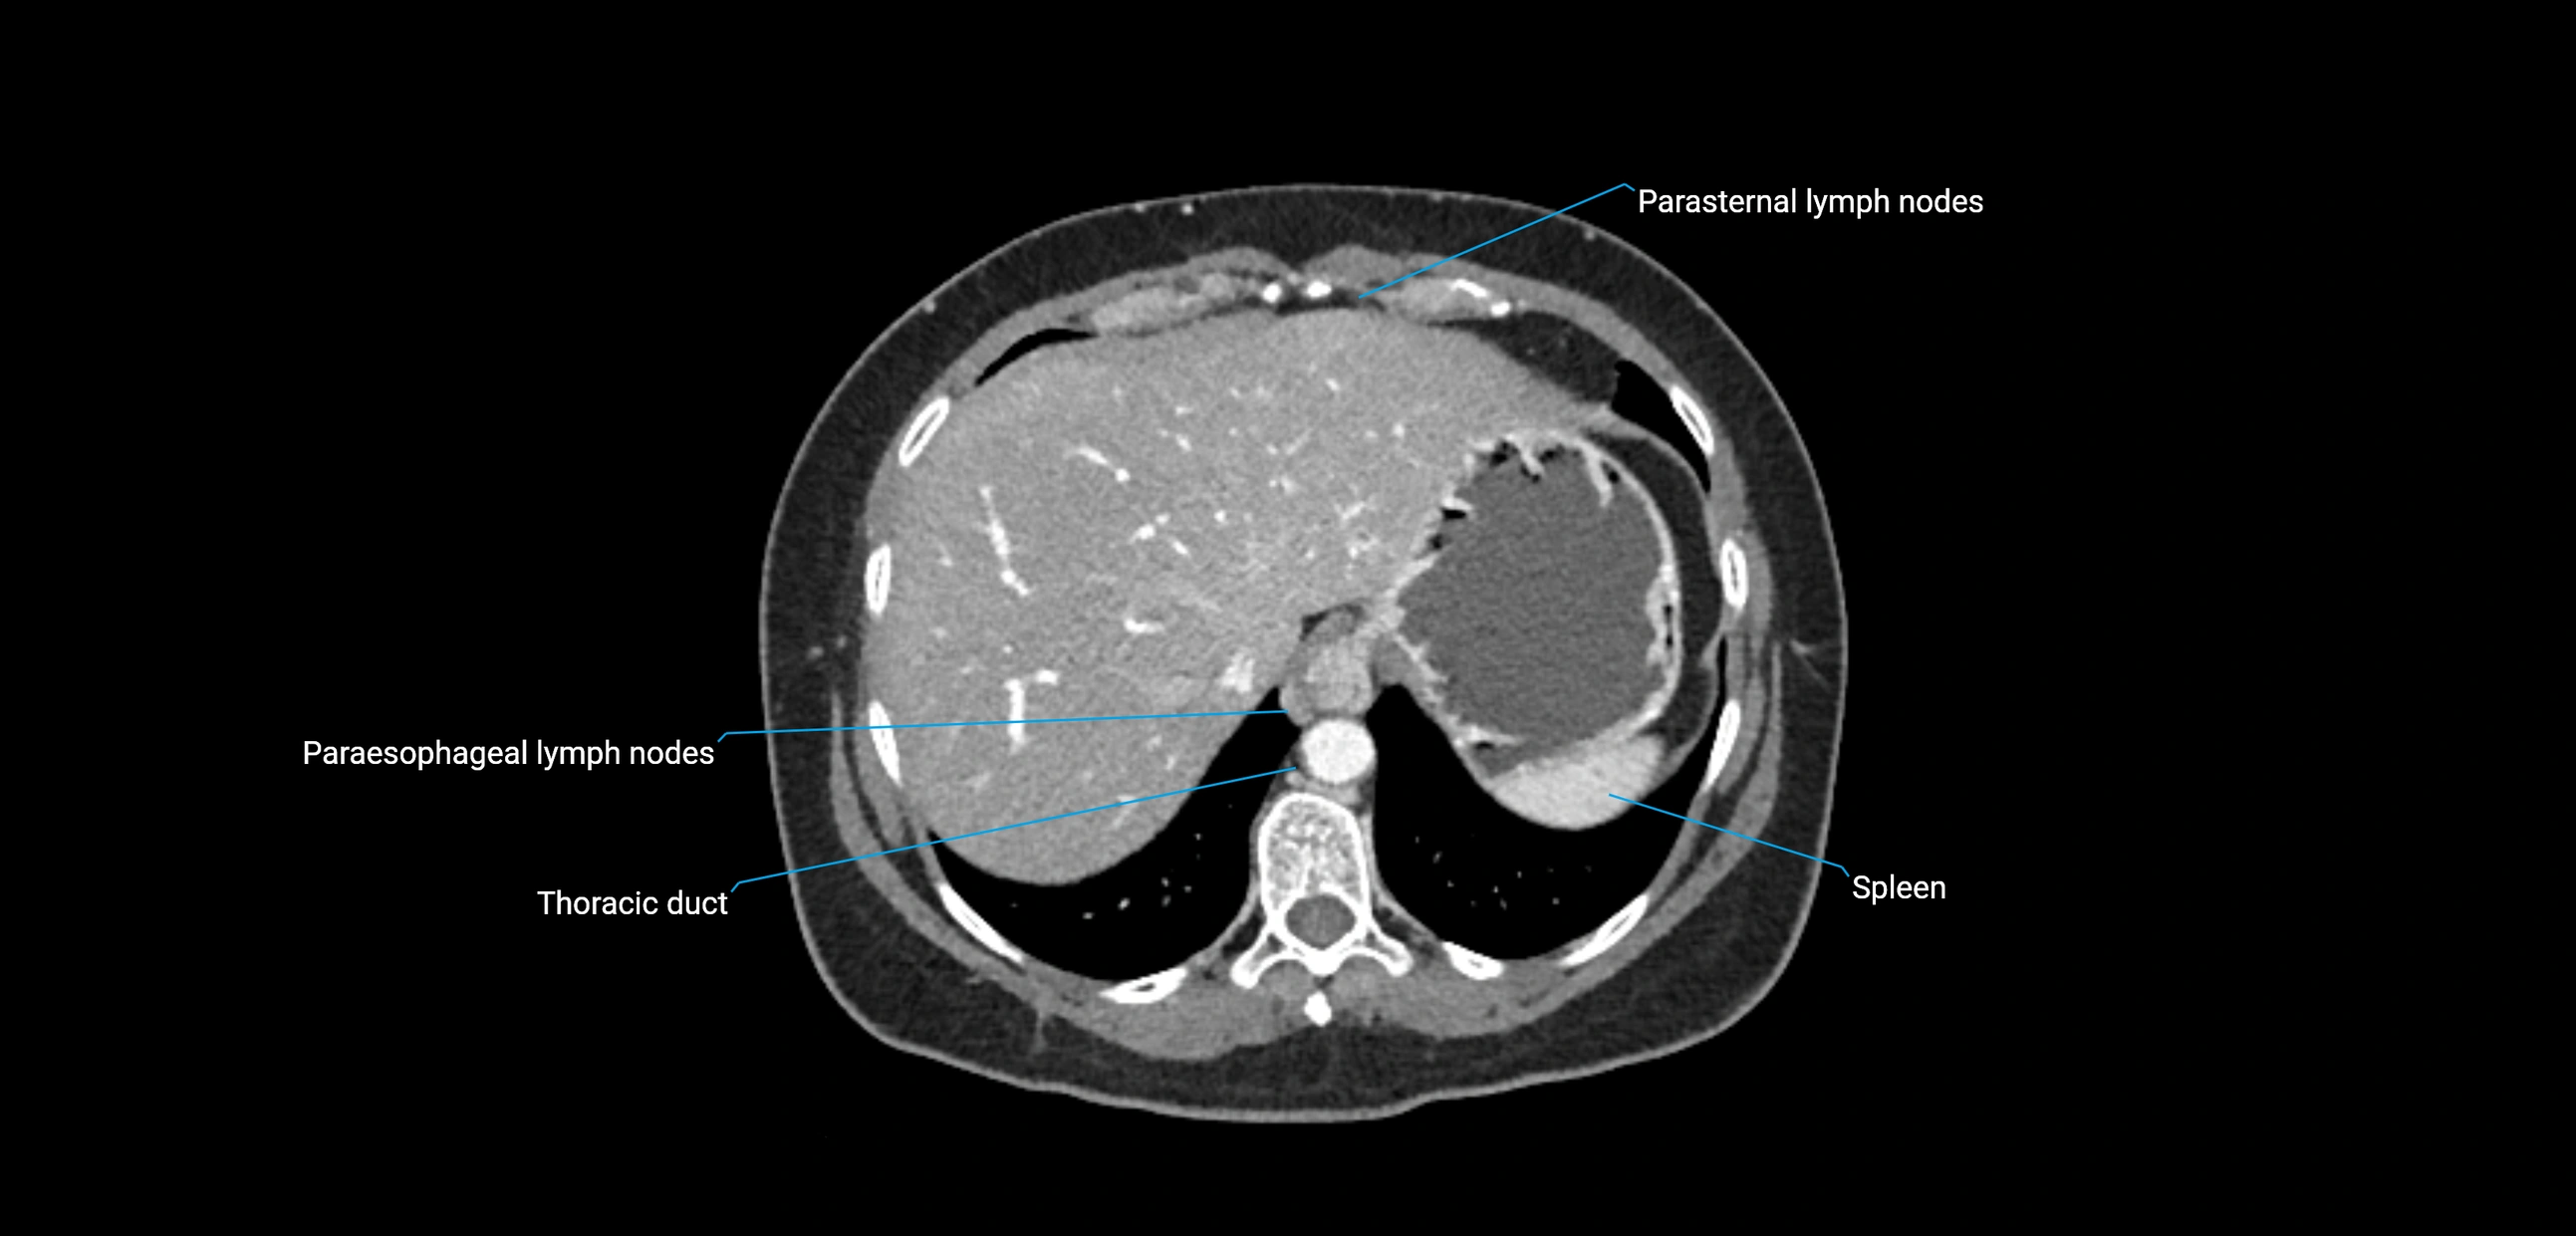

CT Appearance

CT Pre-Contrast:

• Nodes appear as soft-tissue density nodules adjacent to the aorta and IVC

• Calcification may be seen in chronic infections (e.g., tuberculosis)

CT Post-Contrast:

• Normal nodes enhance homogeneously

• Malignant nodes may show heterogeneous enhancement, central necrosis, or conglomerate formation

• Size >1 cm short axis is suspicious, though morphology and distribution are equally important